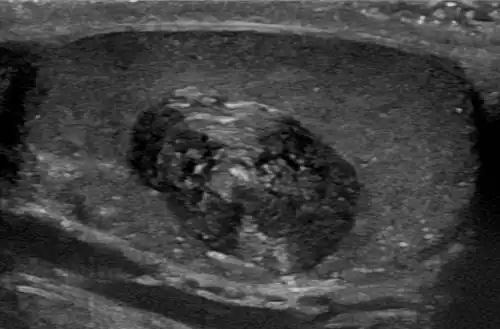

Epidermoid cysts are usually diagnosed when a person notices a bump on their skin and seeks medical attention. The definitive diagnosis is made after excision by a pathologist based on microscopic appearance of a cystic lesion lined by cornified epithelium containing lamellated keratin without calcifications. They can also be seen as isointense lesions on MRI or hyperintensities on FLAIR.